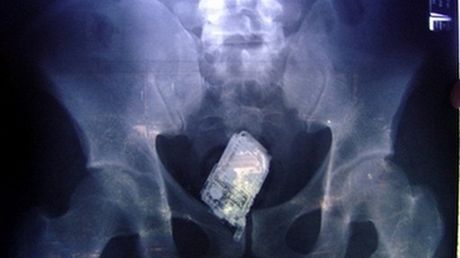

Jeffrey Barrier został przyłapany na robieniu fotek nagiej kobiecie w jednym z salonów piękności w Cincinnati. Natychmiast wezwano policję, a gdy ta przyjechała mężczyzna zarzekał się, że zdarzenie nie miało miejsca, a on nawet nie ma przy sobie telefonu komórkowego. Zgodnie z raportem funkcjonariuszy, Barriera przeszukano dwukrotnie i dopiero za drugim razem stwierdzono, że Amerykanin schował komórkę we własnej odbytnicy.

Mieszkaniec stanu Ohio został postawiony przed sądem i oskarżony o naruszenie prywatności i... utrudnianie śledztwa.